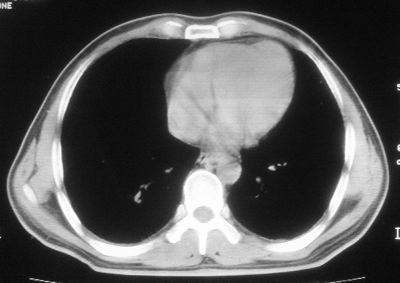

患者,男,44岁,糖尿病4年余,近期消瘦、乏力。化验检查:总胆红素26.33(参考值:5.1-17.2u mol/l),直接胆红素:6.4(参考值:0-4.3u mol/l),谷-丙转氨酶(alt):843(参考值:<40u/l),hbsag(+),抗hbs(-),hbeag(-),抗-hbe(+),抗-hbc(+)。

1\\粟粒性肺结核可能性大,支气管肺泡癌不排除

2\\少量腹水

1.双肺急性粟粒型肺结核;2.少量腹水.